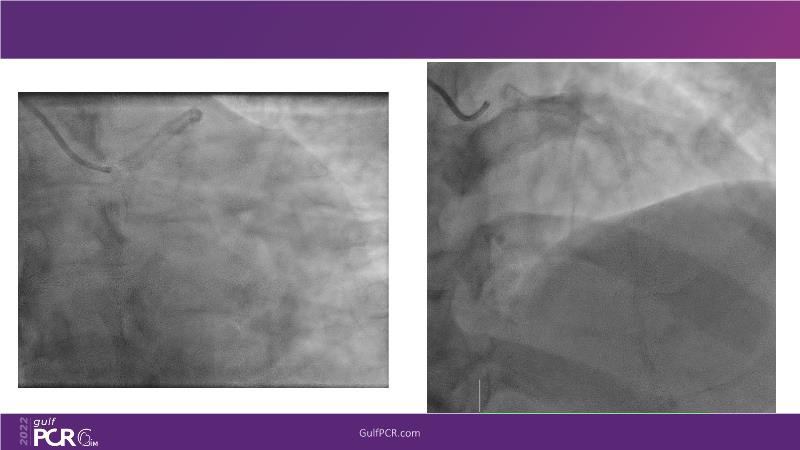

OCT and artificial intelligence: a new shiny light for better decision making in complex coronary interventions

Watch this case-in-point presentation focusing on decision-making in complex PCI using OCT plus AI to understand how to take the right measurement throughout the procedure, how artificial intelligence aids in decision making during imaging-guided PCI, and to gain skills in interpreting OCT imaging, among others!